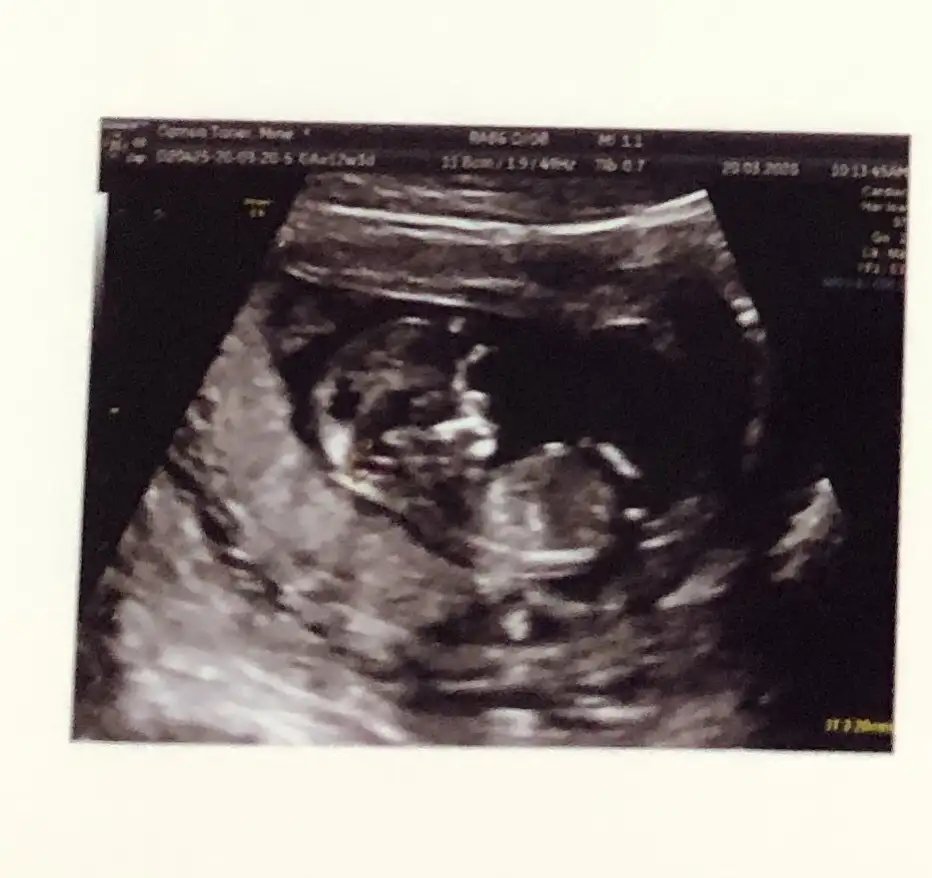

11+3 ama cok net değil gibi sanki yinede Bi tahmin isterim daha 5 hafta sonra öğrencez mecbur 😪

Evet net değil ama emin degilim tahmin ediyorum sanki sanki kız gibi gibi 😬😊

Merhaba bana da tahmin yapar mısınz? 12+1 den bu foto 🥰